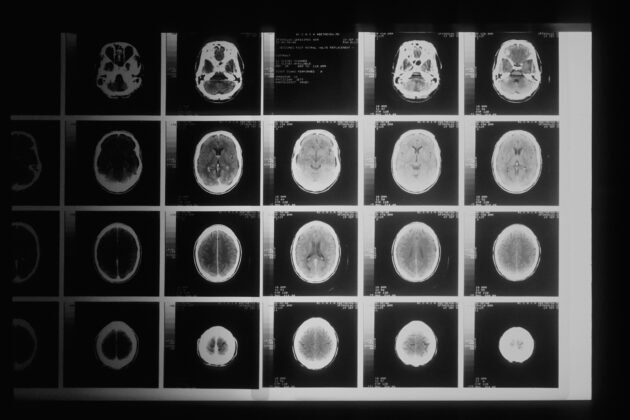

Microsoft made a groundbreaking announcement today regarding its latest artificial intelligence tool, surpassing the diagnostic abilities of a panel of experienced medical doctors. The Microsoft AI Diagnostic Orchestrator (MAI-DxO) demonstrated an impressive accuracy rate of 85.5% in diagnosing complex cases, outperforming the physicians who achieved a correct diagnosis only 20% of the time. Although not yet available for clinical use, this tool represents a significant advancement in the field of medical AI.

Microsoft’s AI tool, MAI-DxO, recently outperformed a group of 21 skilled physicians from the U.S. and UK in diagnosing intricate cases featured in the New England Journal of Medicine. With an accuracy rate of 85.5% compared to the doctors’ 20%, the tool showcases the potential of artificial intelligence in revolutionizing medical diagnostics.

While MAI-DxO’s success is a remarkable achievement, Microsoft emphasized that the tool is not intended to replace healthcare providers but to enhance their capabilities. By automating routine tasks, aiding in diagnosis, and developing personalized care strategies, AI technology like MAI-DxO has the potential to optimize healthcare delivery.

Further research and testing are required before MAI-DxO can be implemented in clinical settings. The tool’s performance against more common medical conditions needs to be evaluated, and regulatory approval is necessary to ensure its safety and effectiveness in practice.

Microsoft’s Vice President of Health, Bay Gross, described MAI-DxO as a proof-of-concept demonstrating that large language models can effectively navigate complex diagnostic challenges in medicine. By following a step-by-step reasoning process akin to expert physicians, AI tools like MAI-DxO show promise in advancing the field of medical diagnostics.